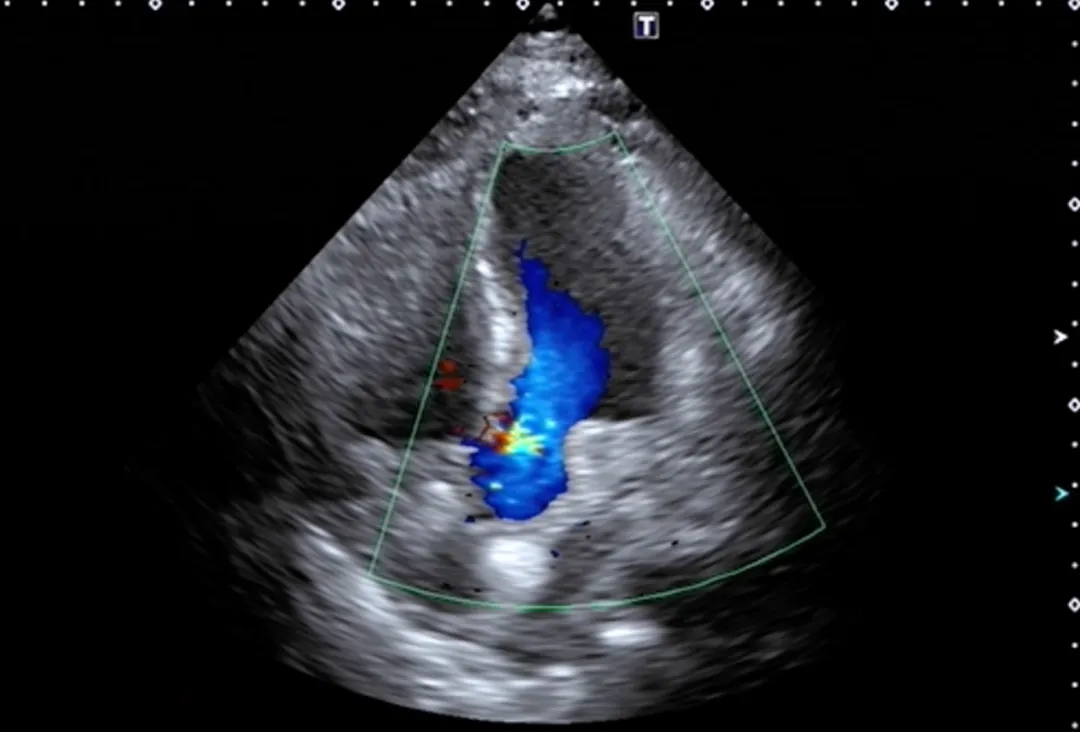

2025-5经食道超声心动图检查:

-

各角度探查左心耳内未见血栓回声。房间隔中段回声纤细,向右房侧膨凸,大小约26x12mm。

第二房间隔呈“搭错样”改变,通道宽约2.8mm,长约12mm。

CDFI:示房水平见左向右分流信号。室间隔连续完整。未见心包积液,无血栓及赘生物。余结构请参阅经胸超声心动图。

超声提示:

房间隔膨出瘤形成

卵圆孔未闭

房水平左向右分流

左心耳内未见血栓回声

2025-5超声右心声学造影检查:发泡实验阳性-心房水平可见右向左分流